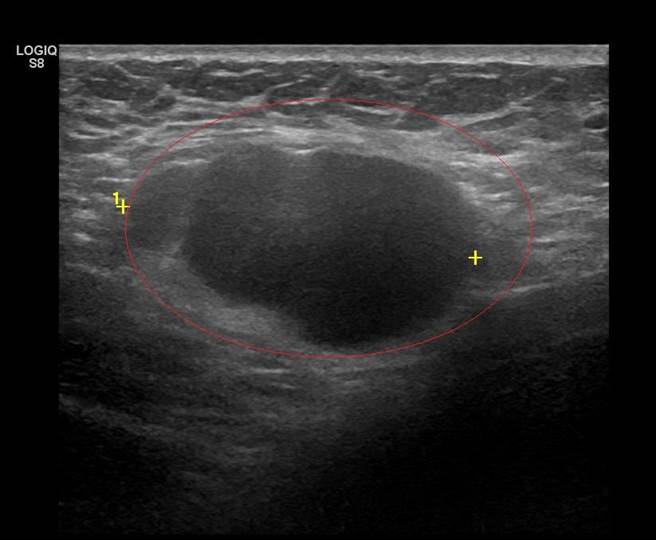

李忠懷表示,經乳房超音波、粗針切片及電腦斷層檢查,證實個案為第三期的乳癌併發腋下淋巴結轉移,乳房腫瘤5公分、淋巴結腫瘤3.2公分,推估腫瘤已存在數月,並非打疫苗引起;目前正透過化療將腫瘤縮小後,再手術切除。

他強調,若為惡性腫瘤轉移,淋巴結皮質會增厚,透過超音波檢查就能看得出來;因此提醒民眾,若施打疫苗後不只是淋巴結腫大,還有身體其他地方也出現腫塊,務必盡快就醫檢查,確認是否為血栓引起,或是有其他病因。